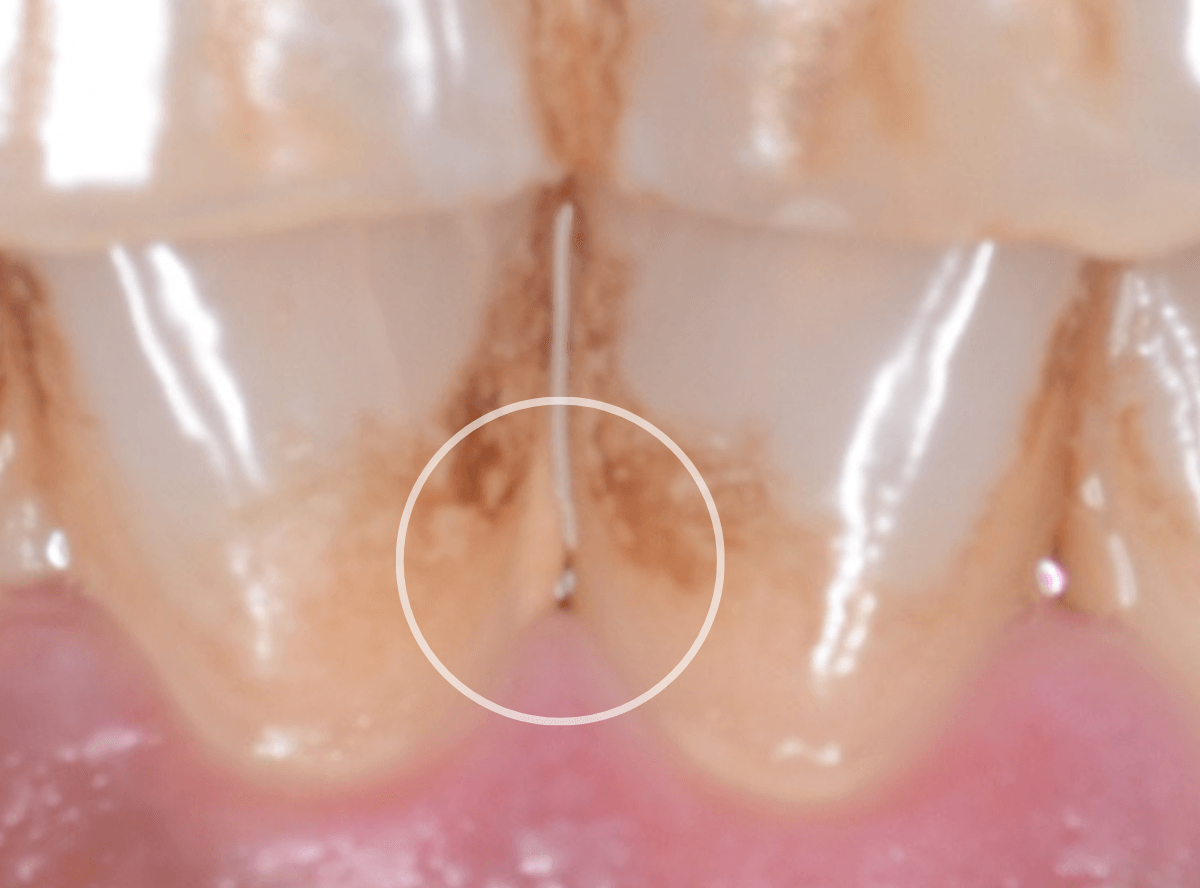

歯石を拡大した様子です。

こちらの方は、着色の割には歯石は少量が表面上にとどまっている状態でしたので、時間をお取りしてしっかり歯周辺をクリーニングする「ビューティー・クリーニング:60分 1万円」をご提案し、選択されました。

60分かけて、歯をクリーニング・仕上げにコーティングをしました。

着色をしっかり除去するのは意外と時間がかかります。お風呂の掃除をイメージしてもらうといいかもしれません。

着色が残っている部分は、歯ではなく虫歯の治療後につめるレジンが変色しているからです。

こちらを綺麗にする場合は、別途レジンのつめ直しが必要です。